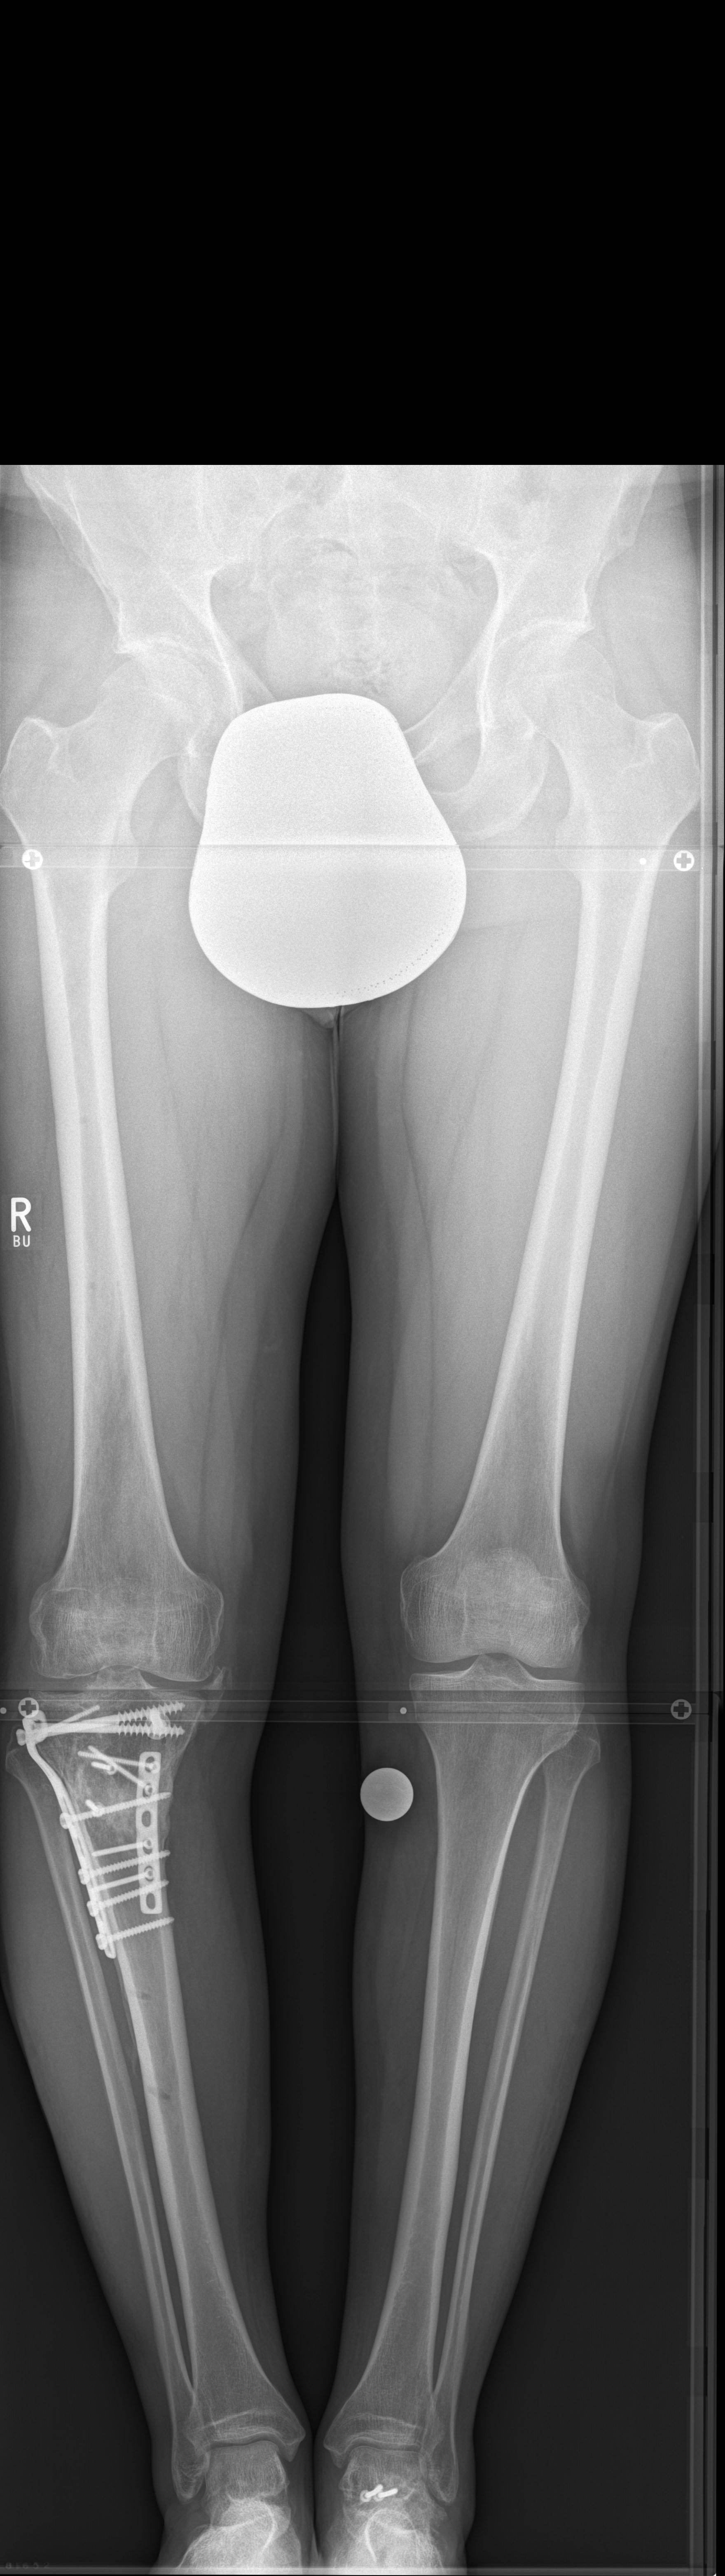

A 52-year-old man with a posttraumatic deformity 2 years after tibial plateau fracture AO/OTA 41C3.3e, PL, PM complained of pain after a normal working day. The patient was a heavy smoker. Activities like sports or hiking were discontinued. Surprisingly ligaments in the coronal and sagittal planes were stable. There was no effusion. Pain was localized in the medial compartment. The range of motion was limited to 0/0/130°. The deformity was corrected with a high tibial osteotomy.

Showcasing a high tibial osteotomy case